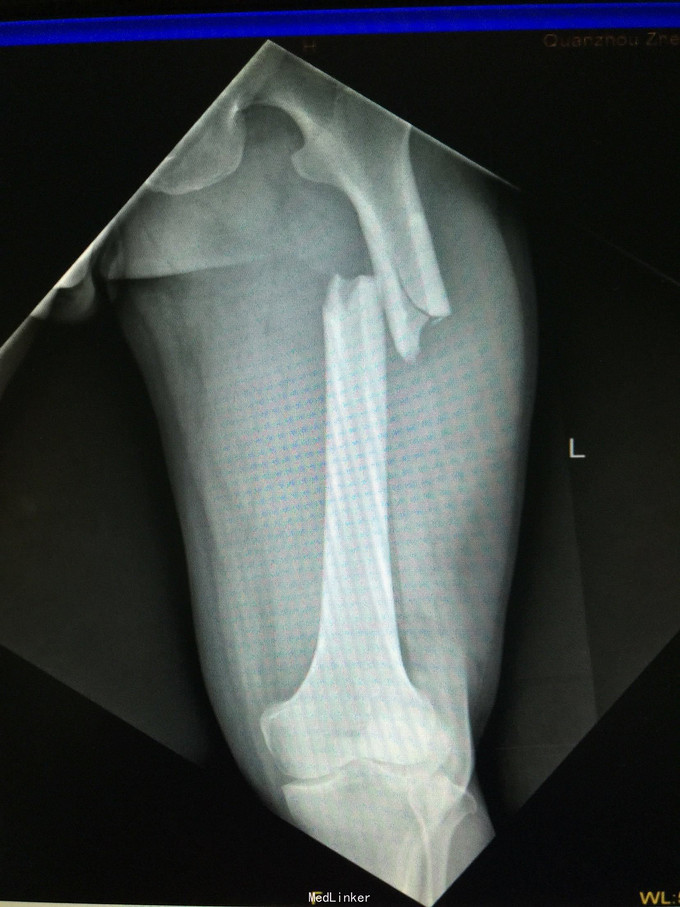

左股骨中上段骨折术后骨不连

主诉:左股骨骨折术后伴局部酸痛11个月

左大腿局部可见手术疤痕,骨折端处无切开疤痕,局部无压痛,无异常活动,关节活动正常。